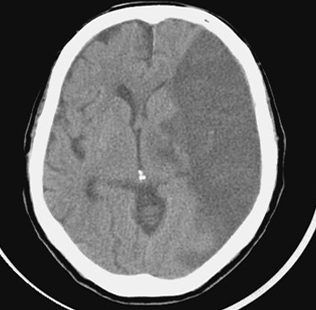

뇌경색 초기증상 모두 정리했어요

이번 포스팅에서 뇌경색 초기증상 모두 알아보려고 해요. 한 번쯤은 뇌경색, 뇌출혈, 뇌졸중에 대해서 들어보신 적이 있을꺼에요.

뇌경색 초기증상이 의심된다면 지금 바로 병원을 내방해 진단을 받고 적절한 치료를 손대는 것이 후유증을 감하는데 중요 해요. 시간이 관건이며, 뇌세포의 괴사, 증상 악화, 너무 늦으면 사망에 이를 수 있는 뇌혈관의 괴사를 피하기 위하여 증상이 나타난 뒤에 4시간 이내에 잘 맞은 약물, 시술 또는 수술을 신속히 실시해야 합니다. 치료로 즉시 하셔야 해요.

현재까지 뇌경색 초기증상에 대하여 알아보았습니다. 뇌경색은 예사로 즉각적인 치료가 필요한 질병으로 자가진단이 쉽지 않다고 하면, 바로 의료기관에 접수한 경우 혹은 아니라면 응급실로 날아가는 것이 좋다고해요.